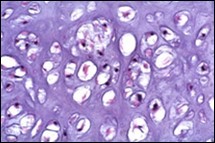

Figure 6.Enchondroma exemplifying lobules of hyaline cartilage composed of enlarged, vacuolated cells with uniform nuclei. Focal calcification is absent 14

Enchondroma exemplifying lobules of hyaline cartilage composed of enlarged, vacuolated cells with               uniform nuclei. Focal calcification is       absent 14